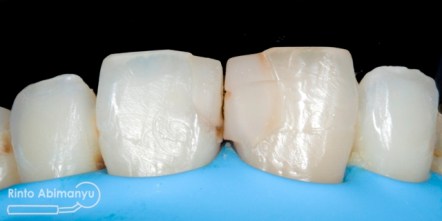

Ini kondisi gigi pada saat datang…

Kondisi awal gigi 11

Terlihat kondisi gigi 11 dan 21 yang ada tambalannya di mesial, ada karies sekunder dan bentuk tambalan tidak mengikuti anatomi gigi 11 dan 21 seharusnya…

Tampak depan sebelum tambalan dibongkar

Setelah tambalan dibongkar dan dibuatkan bevel

Selesai penambalan dan sebelum dilakukan konturing dan pemolesan

Gigi 11 dan 21 setelah selesai konturing dan pemolesan